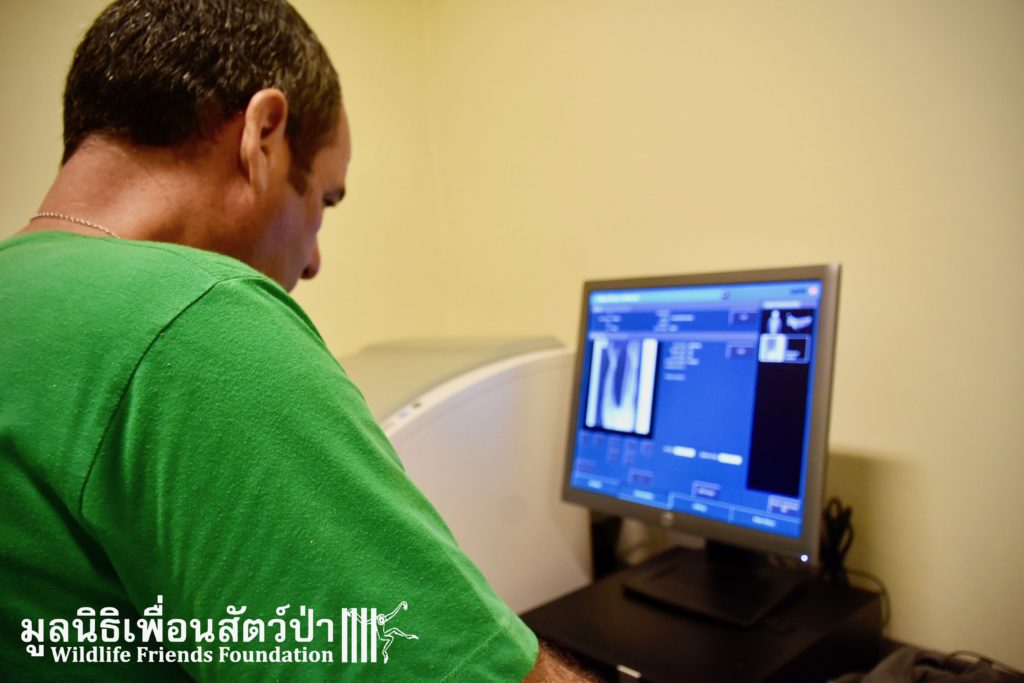

Today we received a call from a compassionate local man who had seen a macaque laying on the ground after being hit by a car. The man sent us photographs of the macaque, the poor monkey was clearly in urgent need of help. The WFFT Wildlife Rescue Team headed out immediately to try and save him. The macaque was next to a temple near Cha-am, approximately 30 minutes away from the WFFT Wildlife Rescue Centre. Upon arrival the team found the adult male long-tailed macaque (Macaca fascicularis) almost motionless. The team loaded him into the rescue vehicle and took him directly to WFFT for an x-ray to determine how severe the injuries were. The results of the x-ray show that nothing was broken. The WFFT Vet Team also checked his health and overall condition. The poor critter, even if without any obvious major injures, will receive the care he deserves and needs till he recovers and be able to return to the wild where he comes from. The health cheek revealed numerous rotten teeth so he will require some dental work before being released back the the wild.